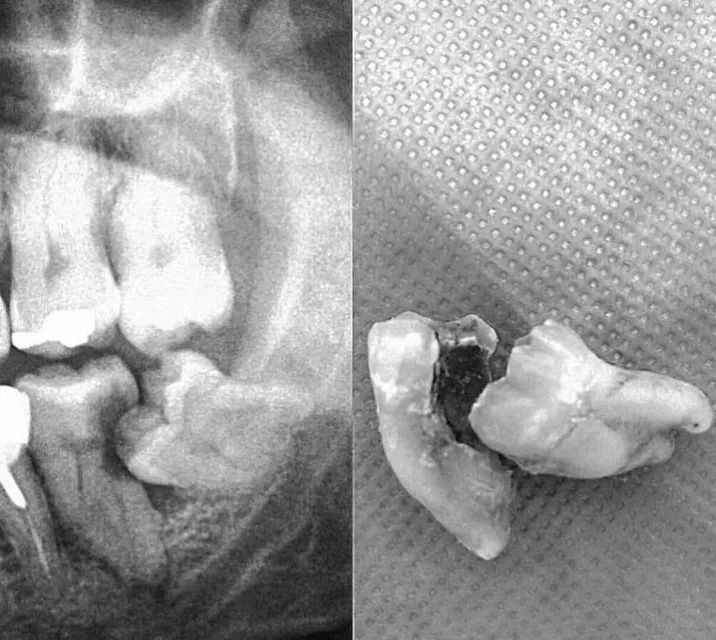

自己不好好长就算了,还会骚扰隔壁邻居

这种智齿必须要拔掉!!!